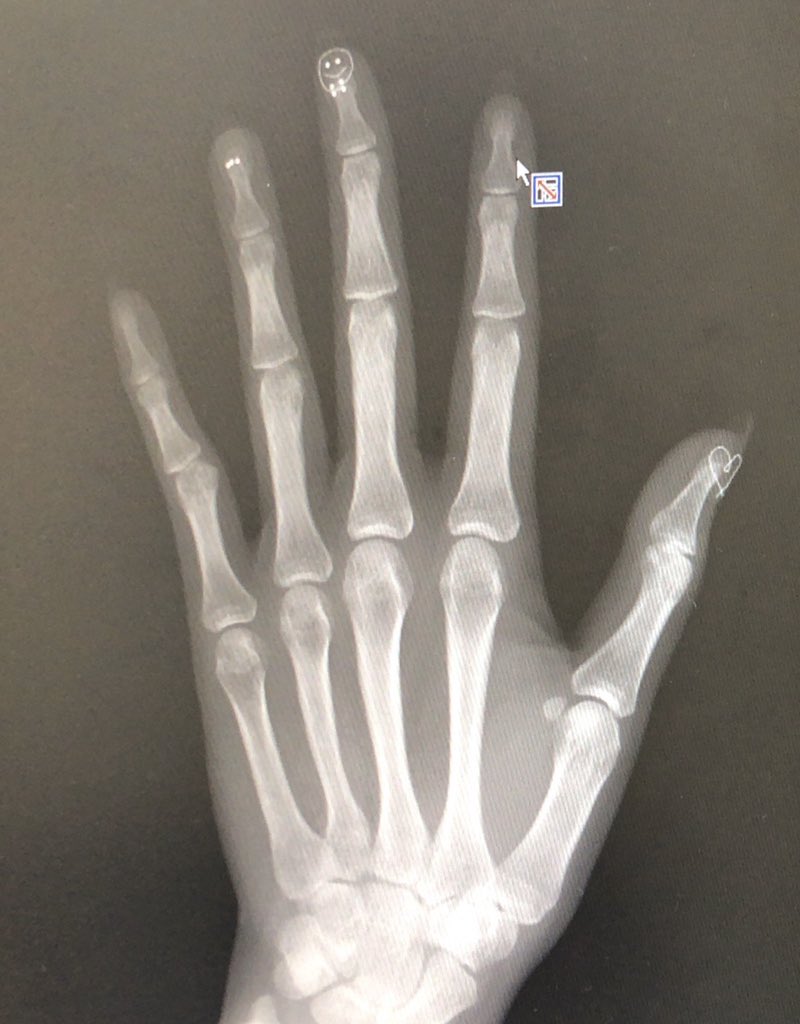

@ny1069p 私もやらかしたことあります😂 https://t.co/GJnJRLEUyO

— あんず (annnnnzu_s2a) 2019年09月17日

https://pbs.twimg.com/media/EEqNtkPU8AAjZXc.jpg